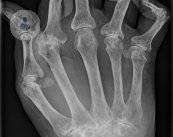

Artritis Reumatoide: qué es, causas, síntomas y tratamiento

¿Sabes que la artritis reumatoide es la enfermedad inflamatoria crónica articular más frecuente? La Dra. Valero Expósito, experta en Reumatología, explica los factores que desencadenan sus síntomas y los tratamientos que existen.